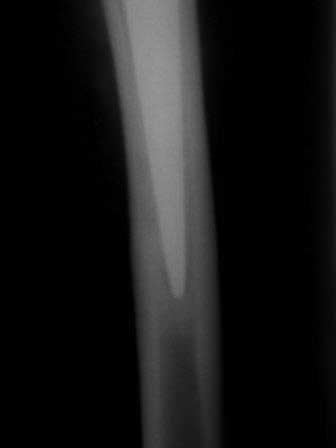

Если не ошибаюсь, то у больной имеется нестабильность бедренного компонента эндопротеза. Стартовые ("помповые") боли, а также зона просветления вокруг цемента и смещение цемента относительно кости...

Здравствуйте! К сожалению, качество рентгенснимков очень низкое,трудно определить есть ли разряжение на границе цементная мантия-кость.

Здравствуйте. Несомненно качество снимков не позволяет определить зону демаркации (если она есть). Делать нагрузочные снимки не вижу смысла, так как объем миграции может мыть незначительным и "на глаз" не определяться. При наличие же значимой (видимой) нестабильности всегда будет выраженная зона демаркации кость-цемент. Имеет смысл сравнить снимки сразу после имплантации и на данный момент. Обнаруженная миграция ножки может быть косвенным признаком возможной нестабильности. Впрочем, насколько я знаю, допускается некоторое "проседание" ножки при безцементом и цементом протезирование с отсутствием болевого синдрома (по типу вторичной фиксации). А вот миграция+боль, почти всегда= нестабильность.

прилагаю рентген снимки сразу после операции в 2009г и февраль 2011г.